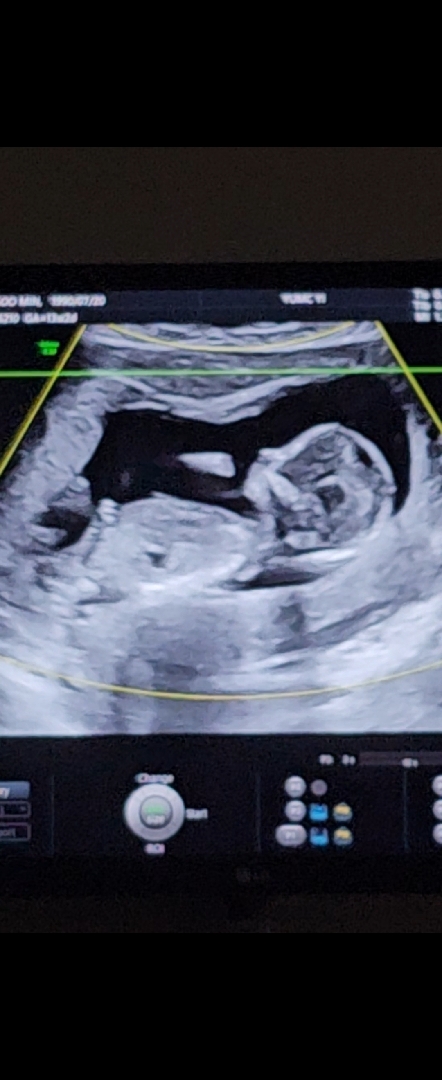

성별 어떻게 보이시나요 🤔 너무 궁금해여 ㅎㅎ

이사진은로 성별볼수 있나요?ㅋ 저도 물어보고싶은데ㅋㅋ어떻게찍어야할지를 모르겠어여ㅋ

성별 너무 궁금합니당 ㅎㅎ